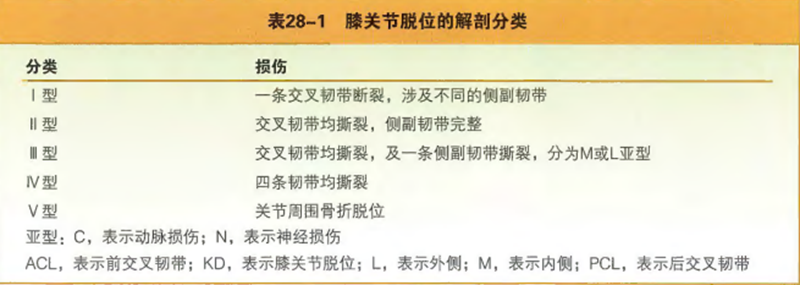

解剖分型是在膝关节解剖结构以及损伤结构的基础上进行分型。包括前交叉韧带、后交叉韧带、内侧结构和后外侧结构。内侧结构包括内侧副韧带的深层和浅层、后内侧关节囊以及斜韧带。后外侧结构包括外侧副韧带、腘腓韧带、腘肌腱及后外侧关节囊。经全面地膝关节损伤评估后,将膝关节的创伤和韧带损伤根据5种可能发生的主要损伤进行解剖分类,按照罗马数字的级别进行分类。

Ⅰ型膝关节脱位为一条交叉韧带完整的脱位(包括前交叉韧带和后交叉韧带完整的损伤)。

Ⅱ型膝关节脱位为两条交叉韧带同时损伤,不伴有侧副韧带损伤。

Ⅲ型膝关节脱位是最常见的类型,涉及两条交叉韧带的损伤并伴有一条侧副韧带的损伤(M或L)。

Ⅳ型膝关节脱位为4条主要的膝关节韧带全部断裂。

Ⅴ型膝关节脱位(被Wascher和Schenck修改),V型膝关节脱位为膝关节脱位伴有关节周围骨折,也有学者将这一型称为骨折伴脱位。

图 膝关节脱位解剖分类

解剖学分类的最后部分是使用亚型来确定相关的神经血管损伤。亚型C表明有显著的动脉损伤并提示临床医生需行血管重建。亚型N表示周围神经损伤,胫神经损伤或者更常见的腓总神经损伤,可用于所有的神经缺陷(神经失用症、神经断裂、轴突断裂)。